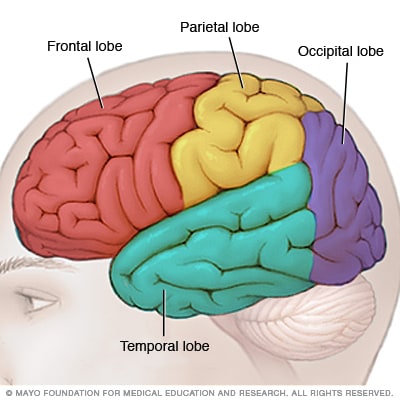

اعرف جسمك الفص الصدغى فى الدماغ يساعد على فهم اللغة والمشاعر اليوم السابع

نوبة الفص الصدغي الأعراض والأسباب Mayo Clinic مايو كلينك